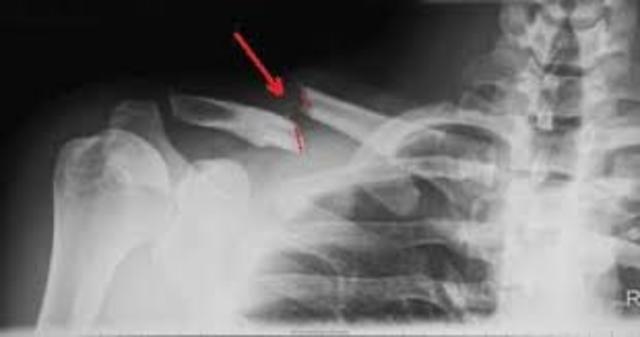

• When I broke my collarbone

When I broke my collarbone

i broke my collarbone in 4th grade